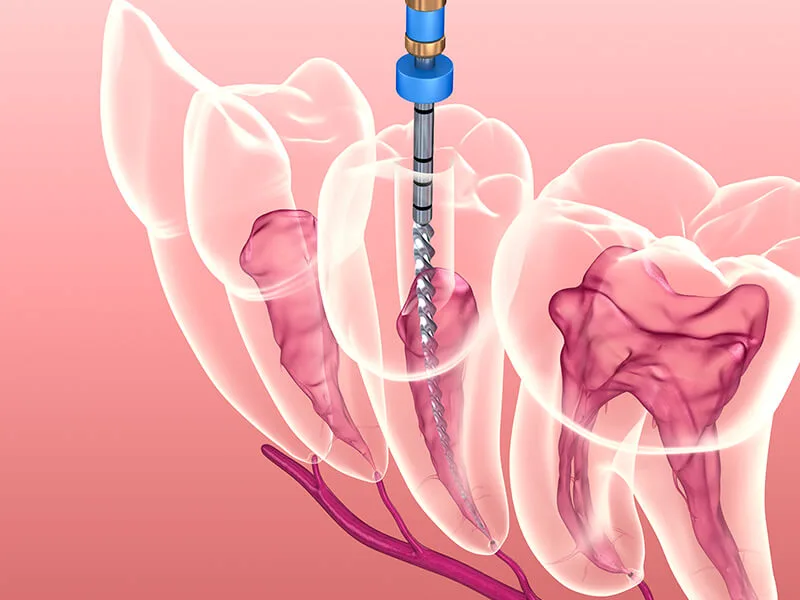

O tratamento remove a polpa infectada e desinfeta os canais radiculares.

Durante o tratamento, você pode esperar um procedimento tranquilo e seguro.

O dentista irá anestesiar a área afetada para assegurar seu conforto.

Após a limpeza e desinfecção, o dente será obturado para proteção.